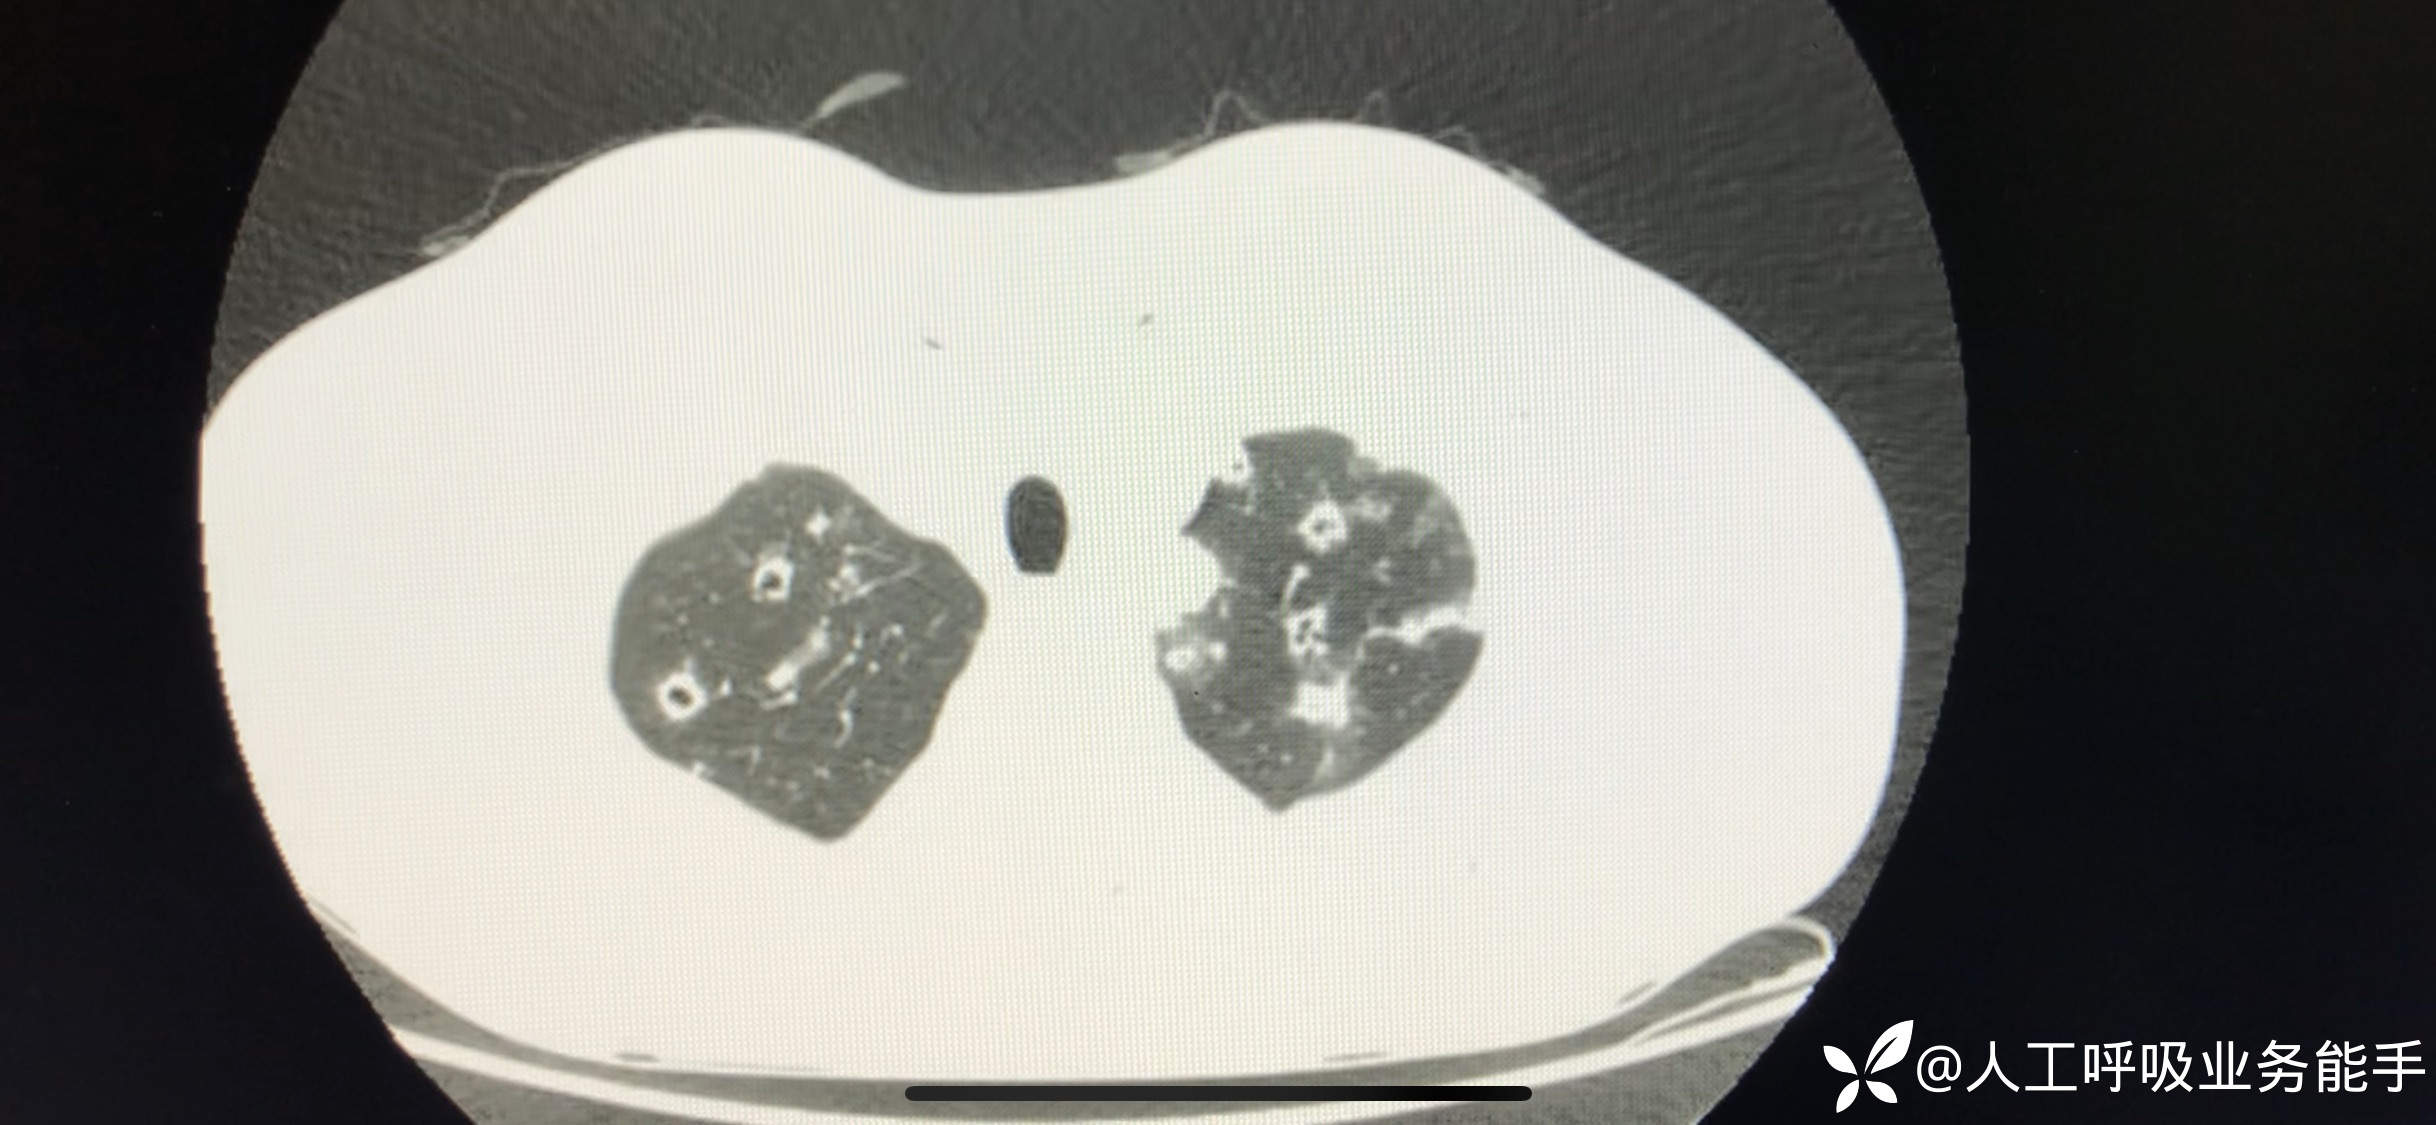

初诊影像: